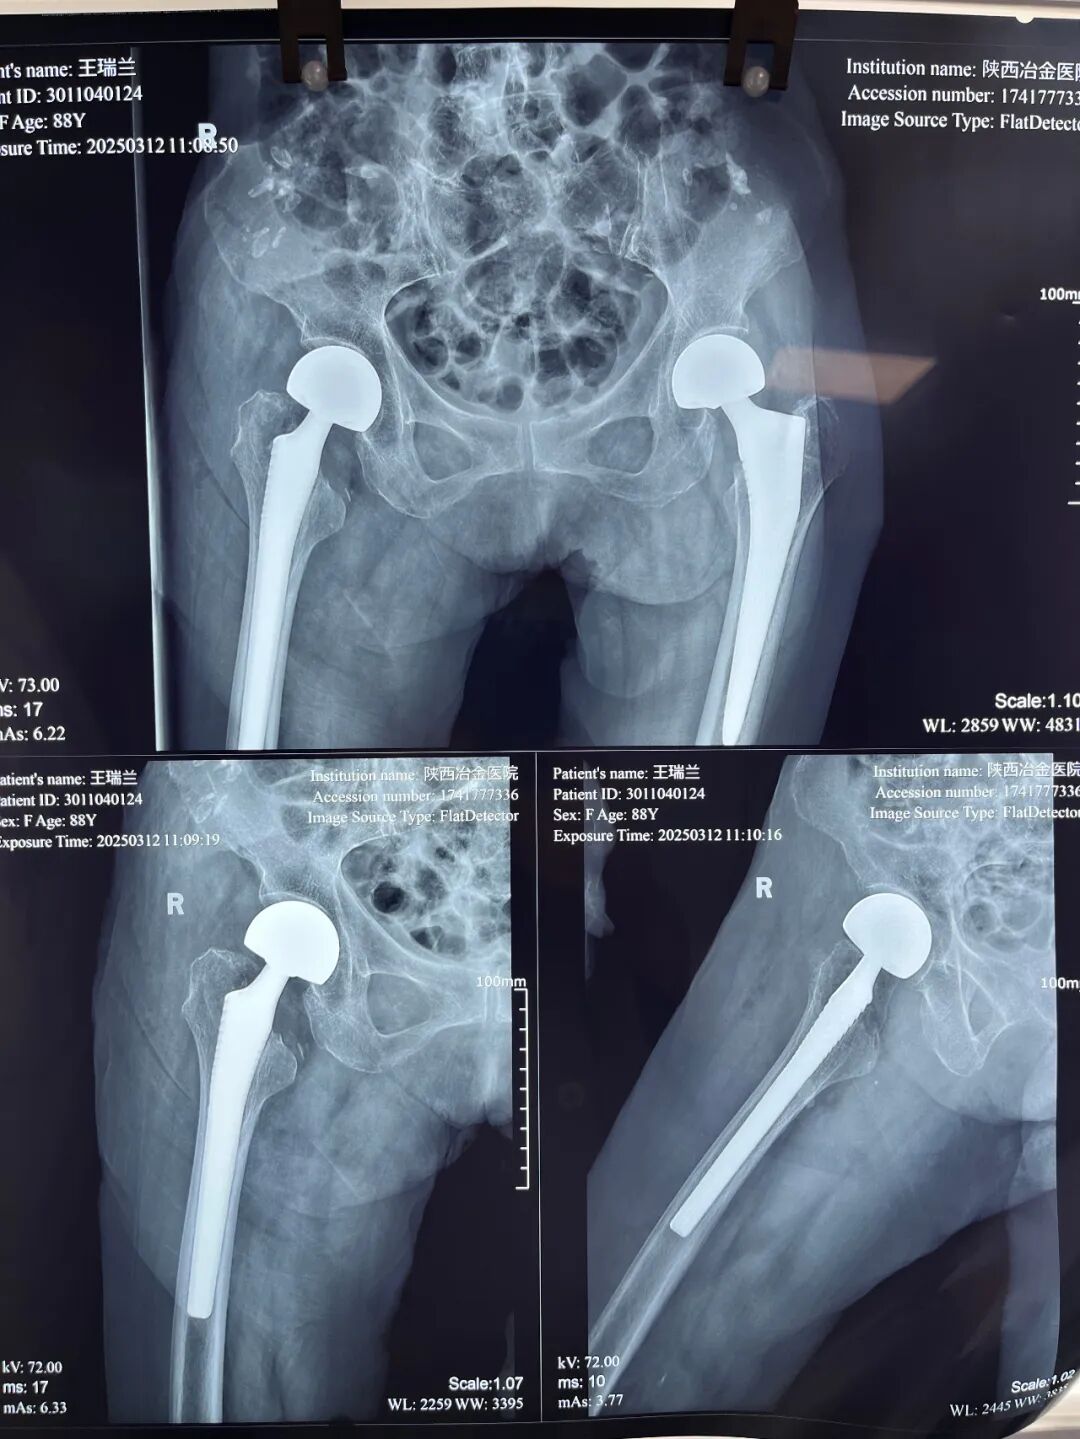

完成右侧股骨头置换术

不久前,家住西安市雁塔区西影路的89岁张奶奶(化名)在家中不慎跌倒,被家人急送至陕西冶金医院骨科就诊。经检查,被诊断为右侧股骨颈骨折。

原来,张奶奶一年半前,左侧股骨颈曾因摔倒发生骨折,在骨科进行手术治疗,术后恢复正常生活,这次又因意外摔倒致右侧股骨颈骨折。

手术当天,在手术麻醉科密切配合下,骨科团队成功为张奶奶实施了股骨头置换术。术后,护理团队精心护理,密切监测生命体征,指导康复训练。

经过骨科医护人员的悉心照料,术后第二天张奶奶即可下床。术后仅三天就已经能够在助行器支持下行走,并在康复师指导下逐步开始康复锻炼。